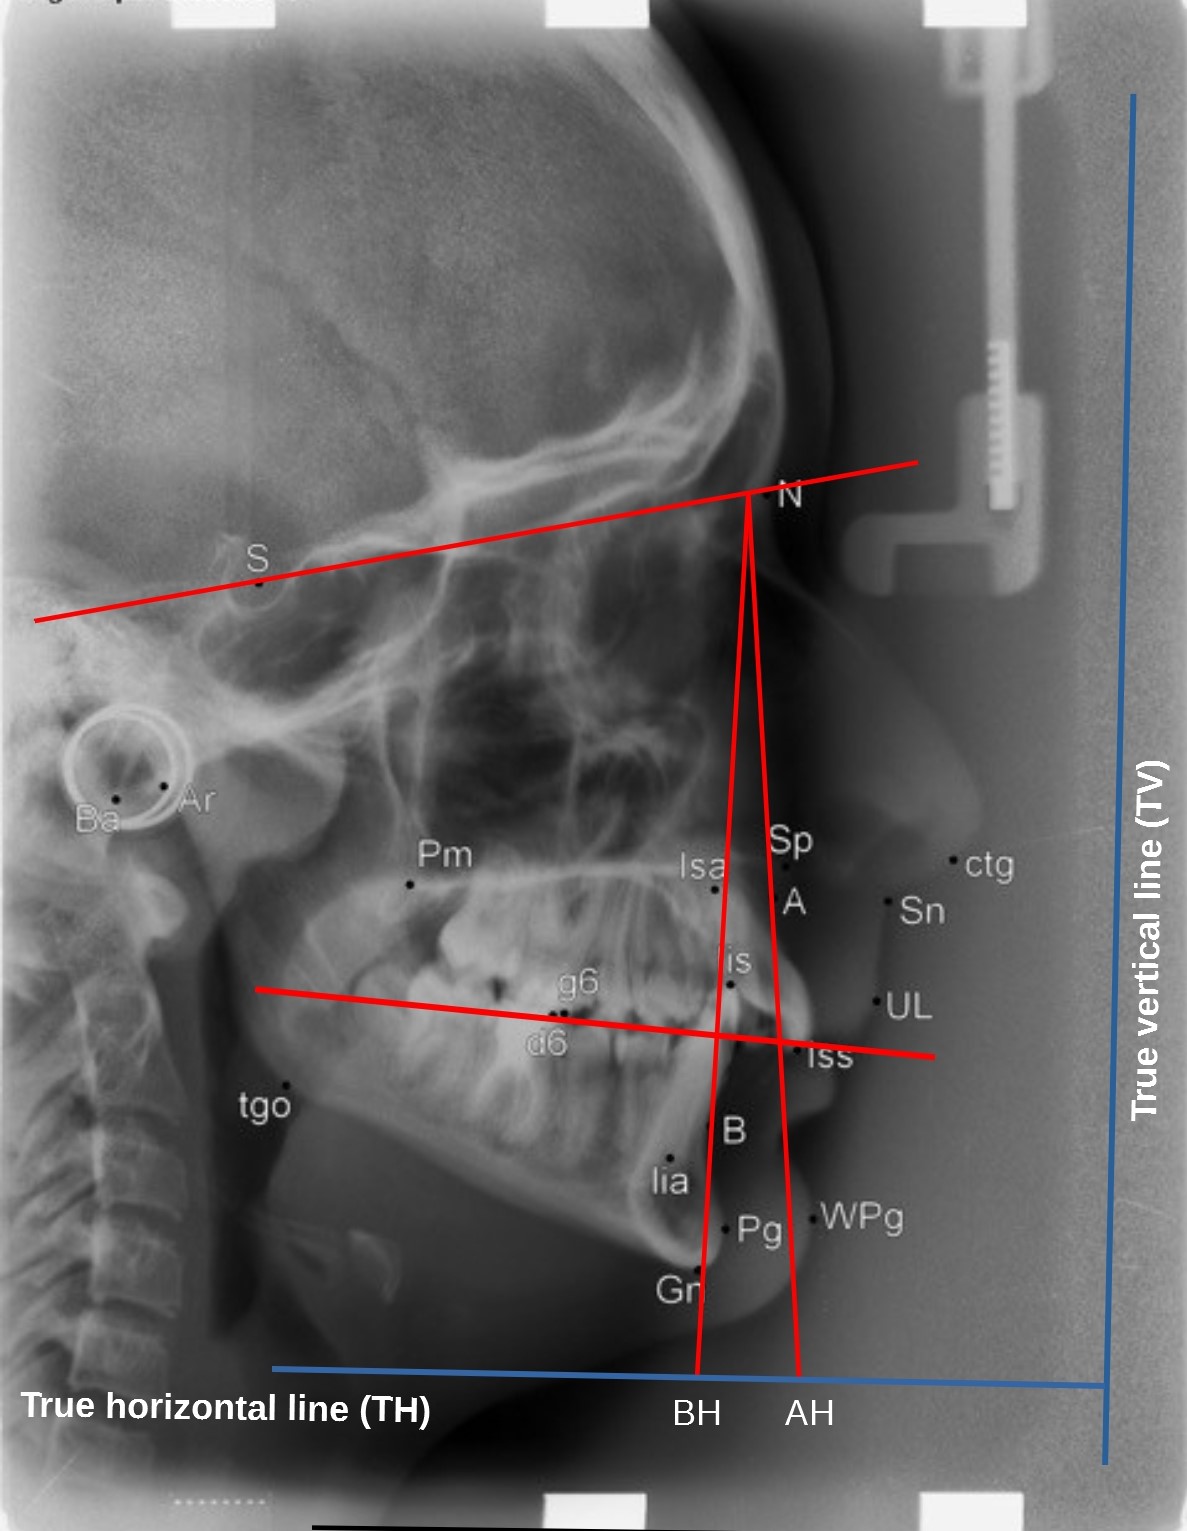

Introductionː Lateral cephalometry is commonly used to analyse craniofacial morphology, soft tissue profile and the direction of facial growth in an attempt to predict the possibilities and limits of orthodontic therapy.

The aim of the study was to present the most frequently used cephalometric measurements to assess the skeletal class on a lateral cephalometric headfilm.

Conclusionsː 1. ANB angle cannot be used as the only indicator of sagittal skeletal discrepancy. 2. WITS appraisal is independent of the variability of cranial base structures, thus may be an important supplement to the diagnosis, although it depends on the variability of the occlusal plane. 3. APDI can reliably distinguish between class I, II and III malocclusions.